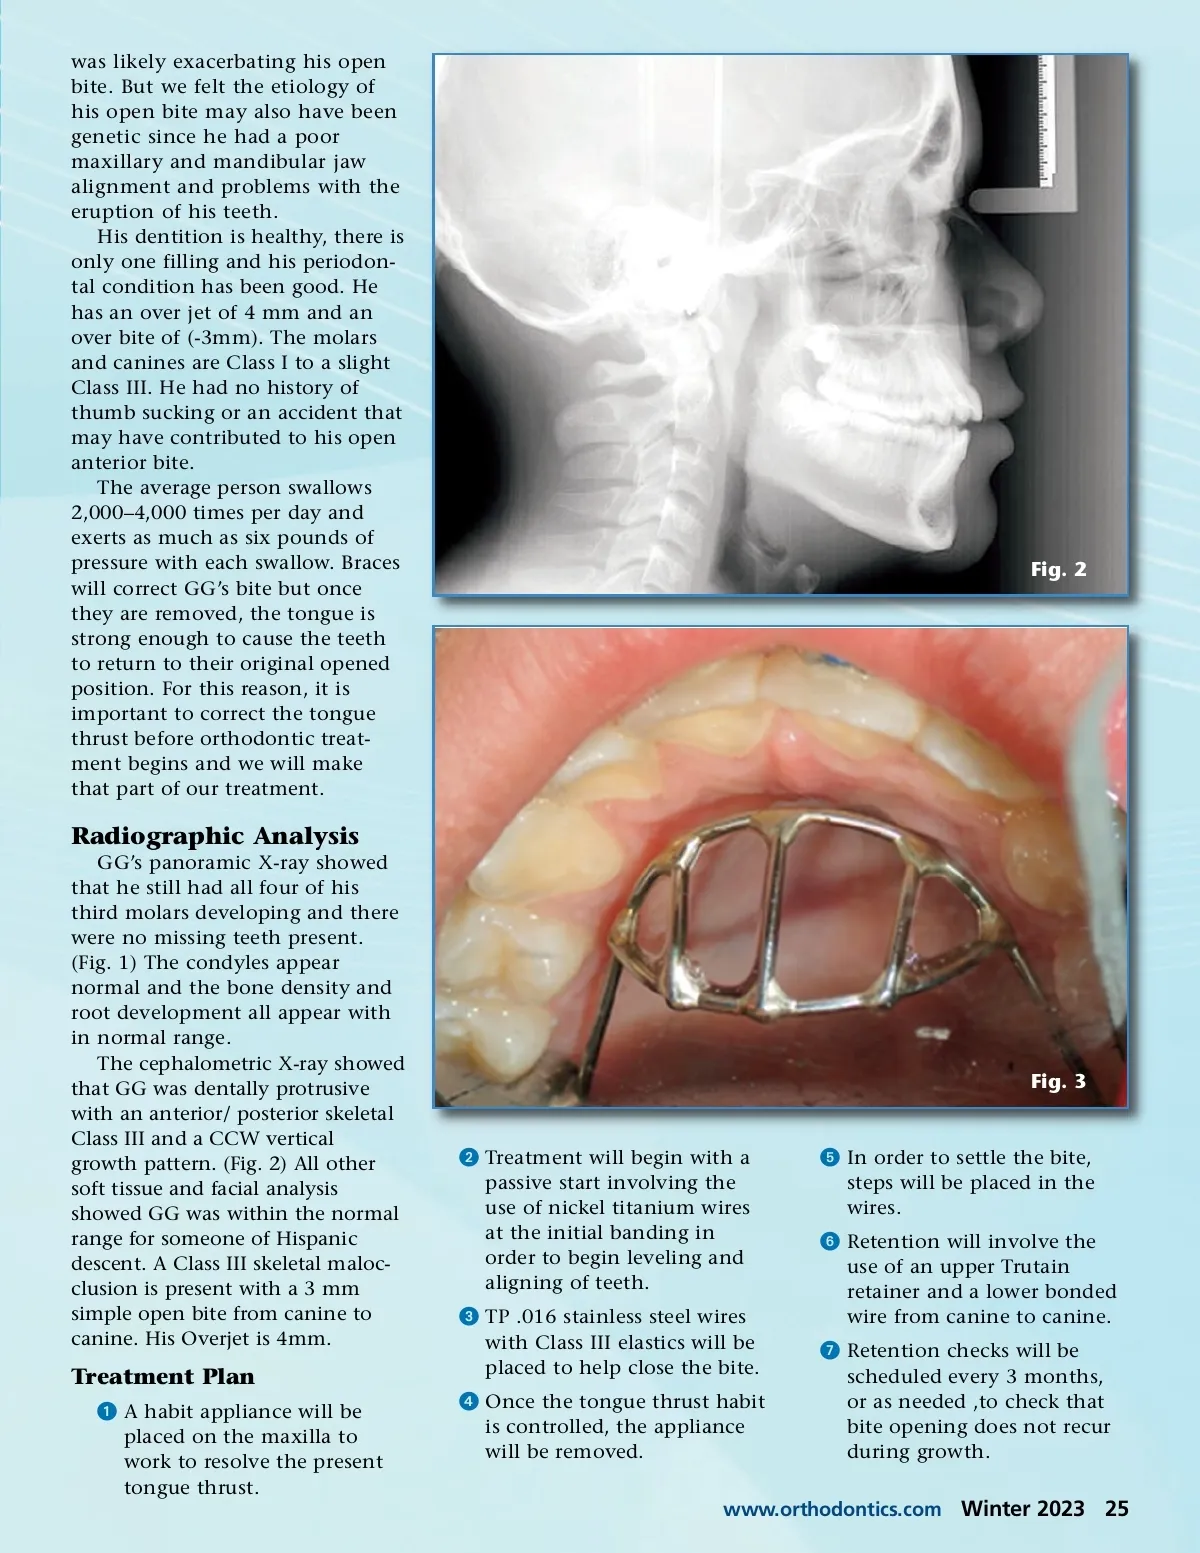

By Jennifer Rand, DMD T he tongue plays an important role in respi-ration, mastication, swallowing and speech. With normal swallowing, the tip of the tongue rests on the lingual part of the maxillary anterior dentoalveolar area; the teeth then come into momentary contact and minimal contraction of the perio-ral muscles occurs. 1 Tongue thrusting is a predomi-nate swallowing pattern in infants, but by the age of 2 – 4 years old, a functional mature swallow develops. A tongue thrust habit is a condition in which the tongue makes contact with any teeth anterior to the molars during swallowing. 2 It has been reported that the Braces will correct GG’s bite but once they are removed, the tongue is strong enough to cause the teeth to return to their original opened position. For this reason, it is important to correct the tongue thrust before orthodontic treatment begins and we will make that part of our treatment. prevalence of tongue thrusting decreases with increasing age. 3 But a prolonged tongue-thrusting habit has been shown to be associ-ated with an open bite; a long facial pattern and the proclination of upper anterior teeth. 4 Clinical Analysis Patient GG came to our office as a 13-year, 9-month-old grow-ing male with a chief complaint of an anterior open bite that extended from canine to canine. He had a tongue thrust habit that Fig. 1 24 Winter 2023 JAOS